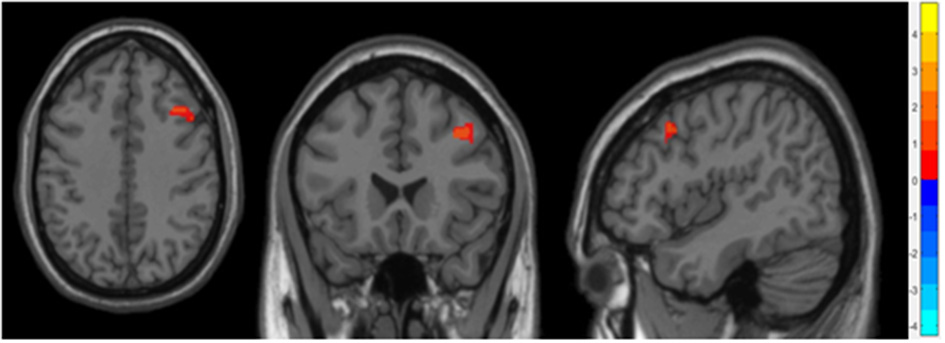

Differences in gray matter volume between groups

Compared to the non-OSA group, the gray matter volume of the right Middle Frontal Gyrus (MFG_R) was increased in the children with OSA (P < 0.05, GRF correction; Table 2 and Figure 1).

Figure 1

It showed the difference regions of GMV in slices with various directions between the OSA and non-OSA groups (P < 0.05, GRF corrected). The red clusters indicate a larger GMV for children with OSA than for controls.